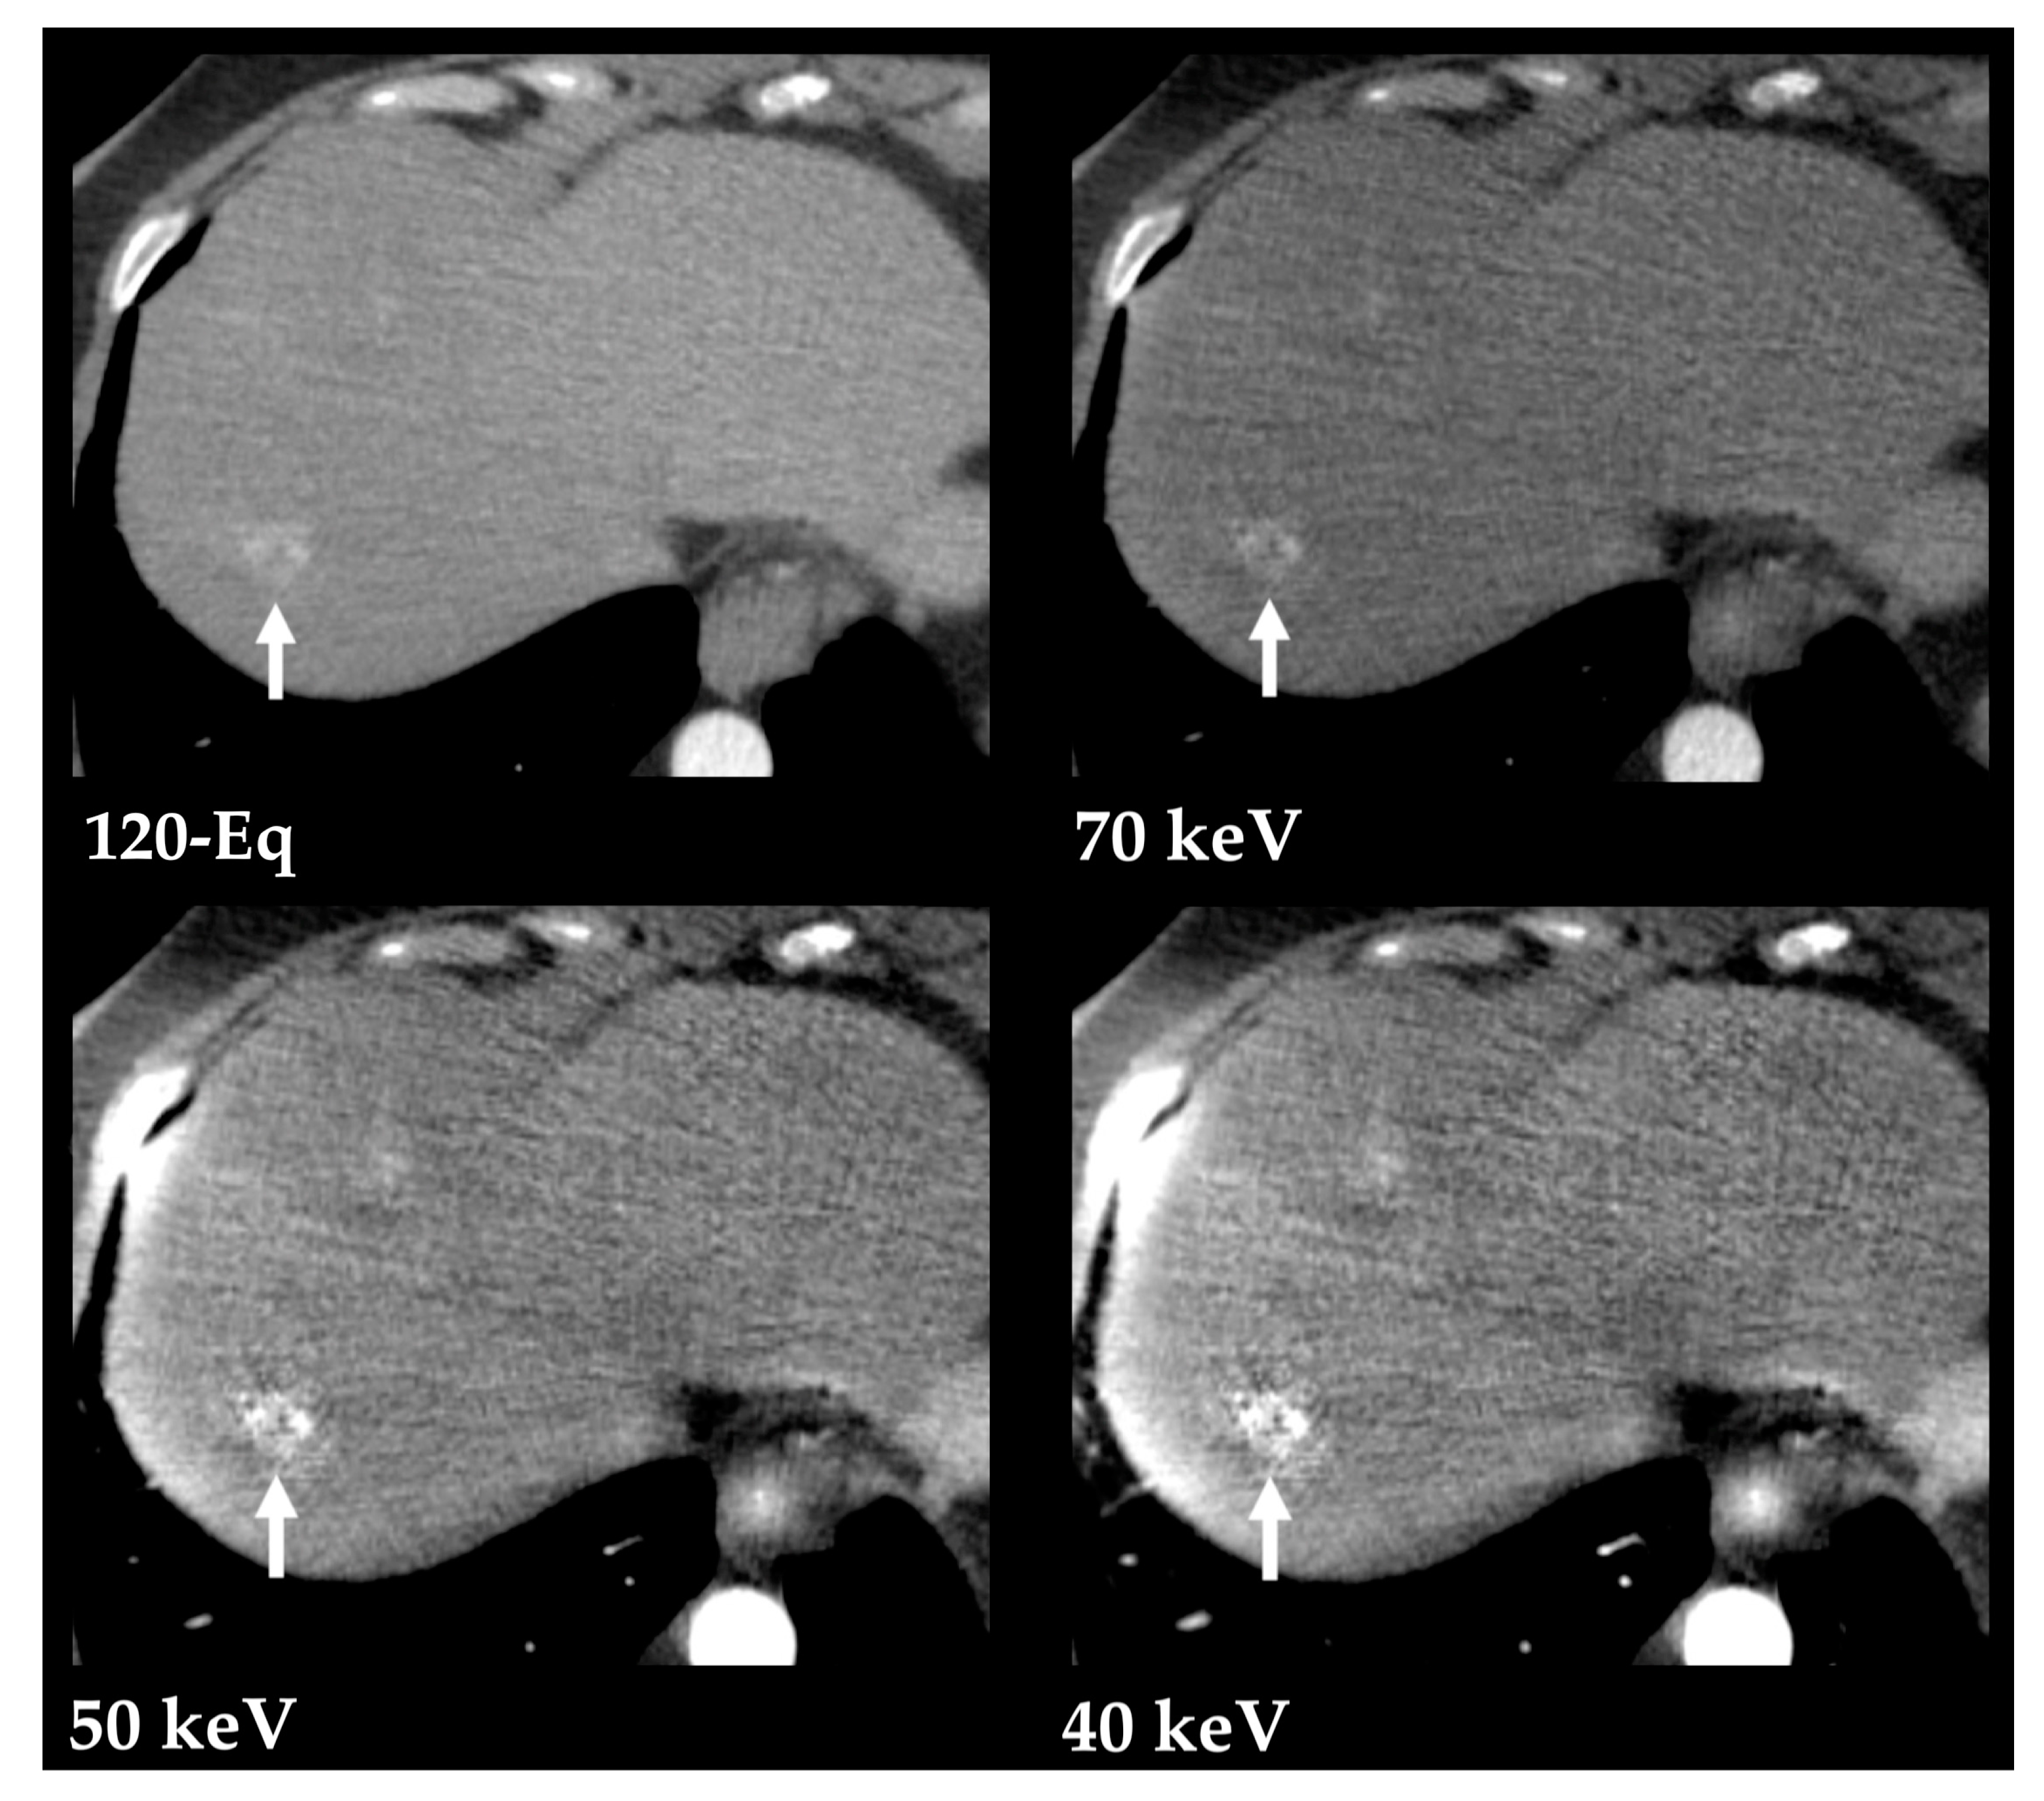

- Große Hokamp, N.; Höink, A.J.; Doerner, J.; Jordan, D.W.; Pahn, G.; Persigehl, T.; Maintz, D.; Haneder, S. Assessment of arterially hyper-enhancing liver lesions using virtual monoenergetic images from spectral detector CT: Phantom and patient experience. Abdom. Radiol. 2018, 43, 2066–2074. [Google Scholar] [CrossRef]

- Shuman, W.P.; Green, D.E.; Busey, J.M.; Mitsumori, L.M.; Choi, E.; Koprowicz, K.M.; Kanal, K.M. Dual-energy liver CT: Effect of monochromatic imaging on lesion detection, conspicuity, and contrast-to-noise ratio of hypervascular lesions on late arterial phase. Am. J. Roentgenol. 2014, 203, 601–606. [Google Scholar] [CrossRef]

- Mileto, A.; Nelson, R.C.; Samei, E.; Choudhury, K.R.; Jaffe, T.A.; Wilson, J.M.; Marin, D. Dual-energy MDCT in hypervascular liver tumors: Effect of body size on selection of the optimal monochromatic energy level. Am. J. Roentgenol. 2014, 203, 1257–1264. [Google Scholar] [CrossRef]

- De Cecco, C.N.; Caruso, D.; Schoepf, U.J.; De Santis, D.; Muscogiuri, G.; Albrecht, M.H.; Meinel, F.G.; Wichmann, J.L.; Burchett, P.F.; Varga-Szemes, A.; et al. A noise-optimized virtual monoenergetic reconstruction algorithm improves the diagnostic accuracy of late hepatic arterial phase dual-energy CT for the detection of hypervascular liver lesions. Eur. Radiol. 2018, 28, 3393–3404. [Google Scholar] [CrossRef]

- Marin, D.; Ramirez-Giraldo, J.C.; Gupta, S.; Fu, W.; Stinnett, S.S.; Mileto, A.; Bellini, D.; Patel, B.; Samei, E.; Nelson, R.C. Effect of a Noise-Optimized Second-Generation Monoenergetic Algorithm on Image Noise and Conspicuity of Hypervascular Liver Tumors: An In Vitro and In Vivo Study. Am. J. Roentgenol. 2016, 206, 1222–1232. [Google Scholar] [CrossRef]

- Voss, B.A.; Khandelwal, A.; Wells, M.L.; Inoue, A.; Venkatesh, S.K.; Lee, Y.S.; Johnson, M.P.; Fletcher, J.G. Impact of dual-energy 50-keV virtual monoenergetic images on radiologist confidence in detection of key imaging findings of small hepatocellular carcinomas using multiphase liver CT. Acta Radiol. 2022, 63, 1443–1452. [Google Scholar] [CrossRef] [PubMed]